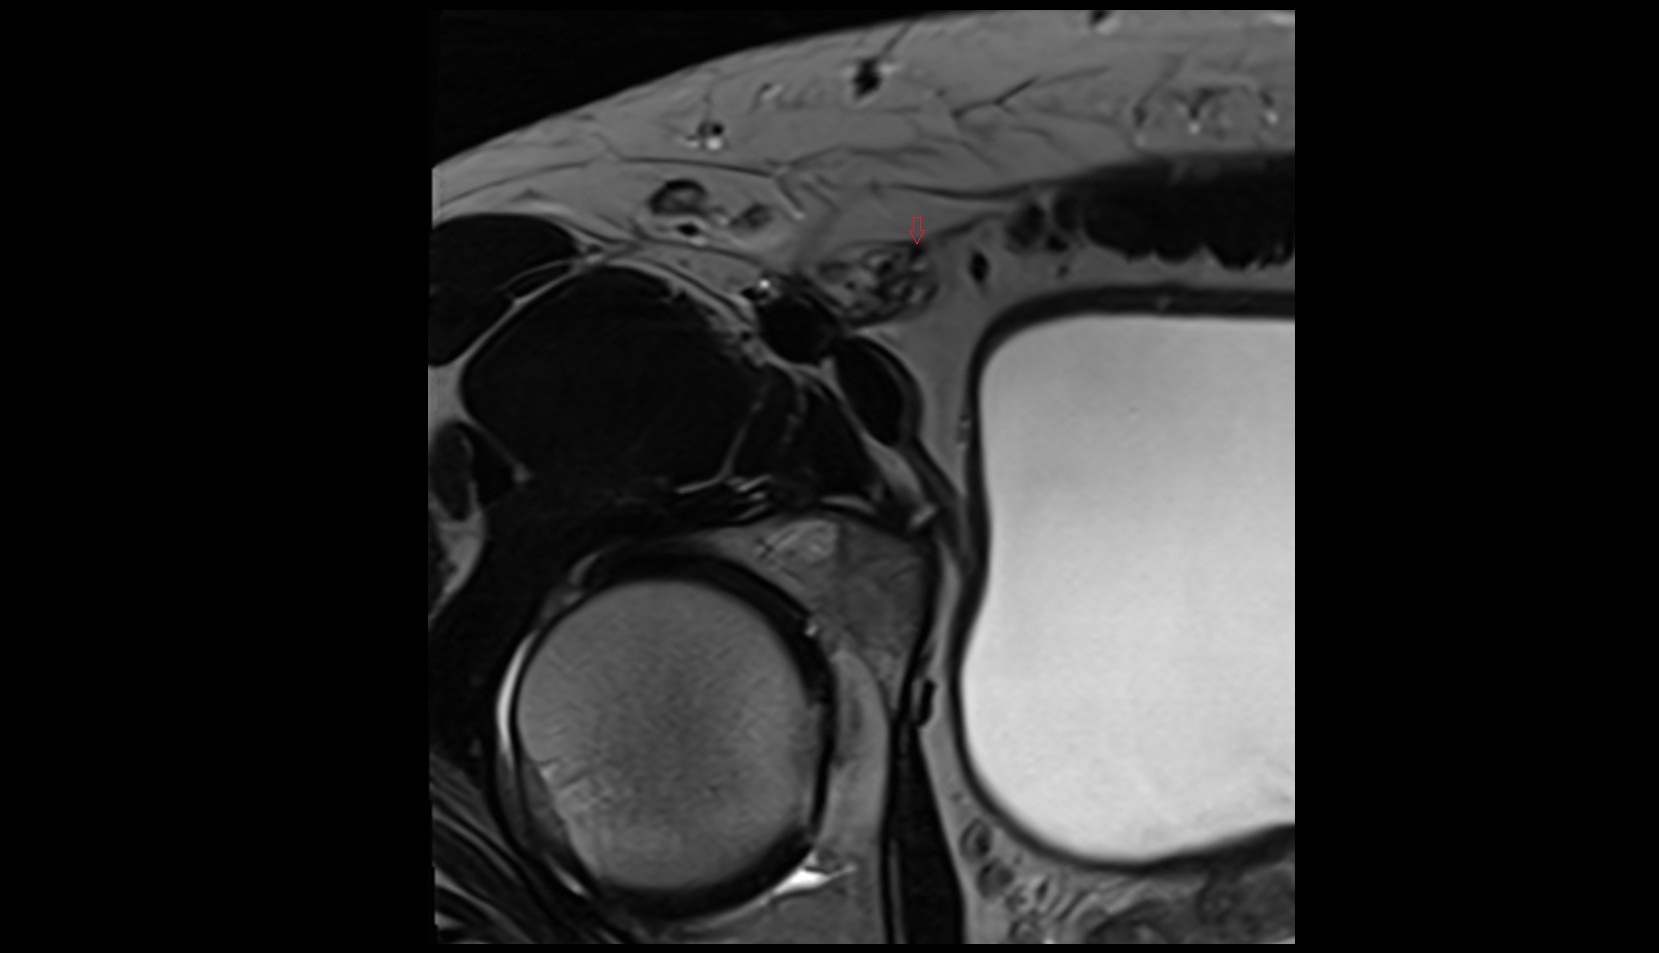

- Shoulder joint (glenohumeral joint)

- Acromioclavicular joint

- Glenoid labrum

- Glenohumeral joint capsule

- Supraspinatus tendon

- Infraspinatus tendon

- Subscapularis tendon